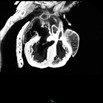

Caption Play MovieSerial 2D EFIC image stack of 227-007-NC in the coronal plane reveals dextrocardia, DORV, AVSD (subaortic) {A,L,L}